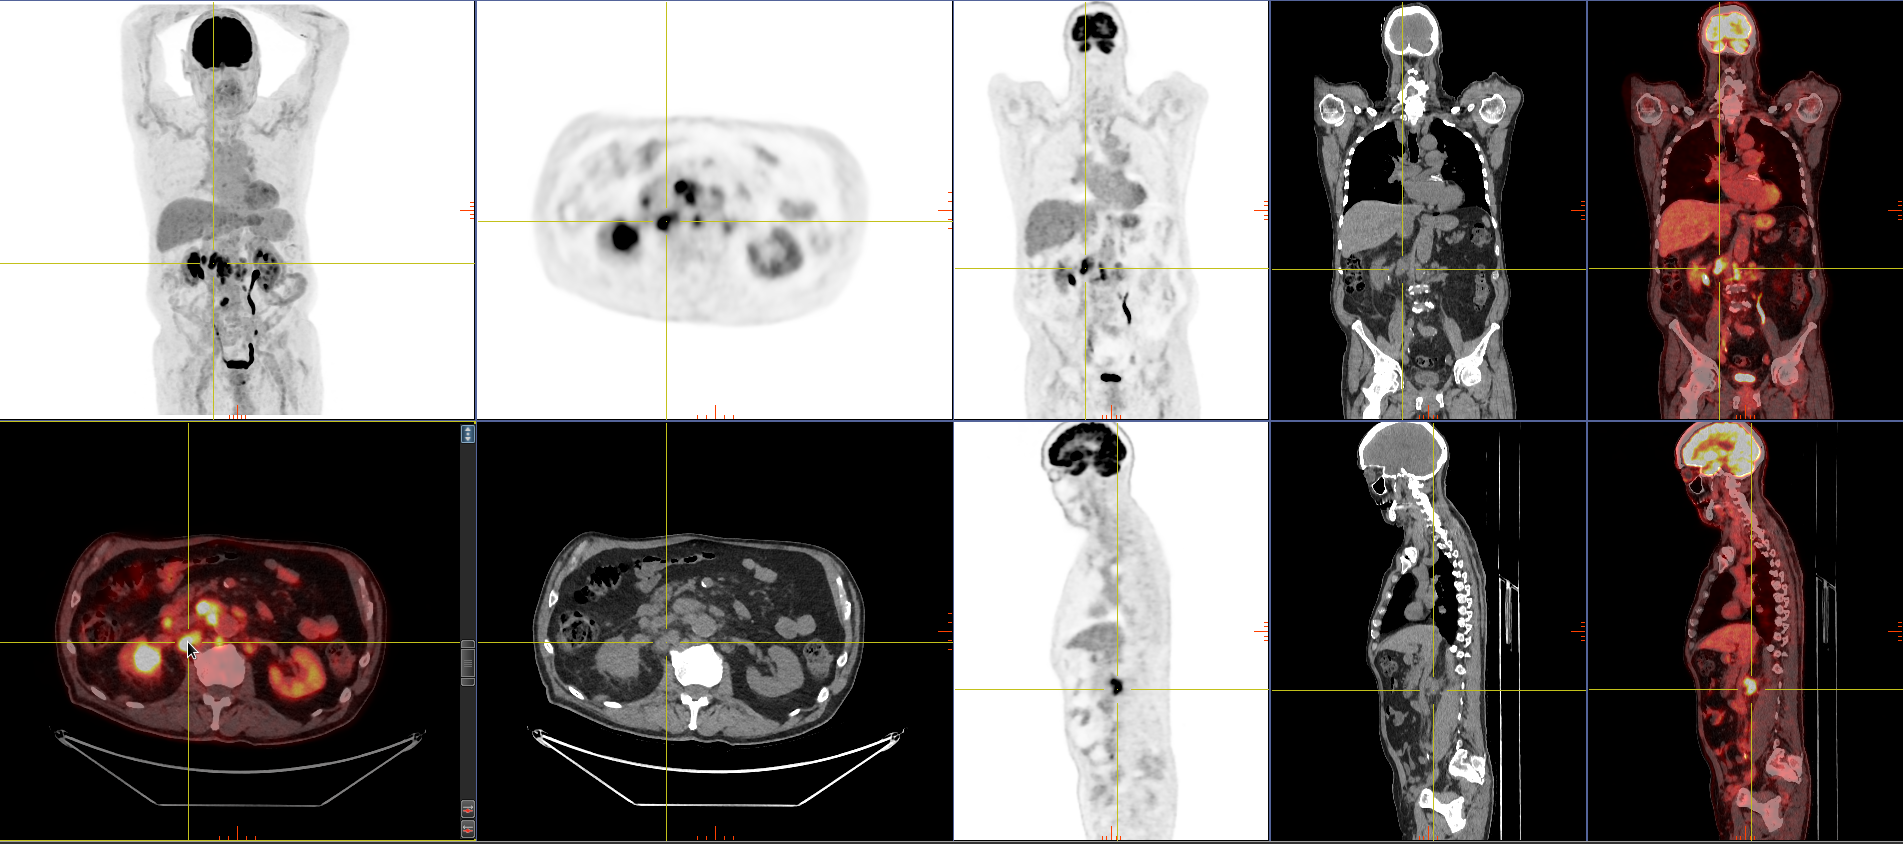

At SRNM, we offer Medicare-funded FDG PET scans (Items 61612 & 61614) for the staging, treatment response, and recurrence of rare and uncommon cancers.